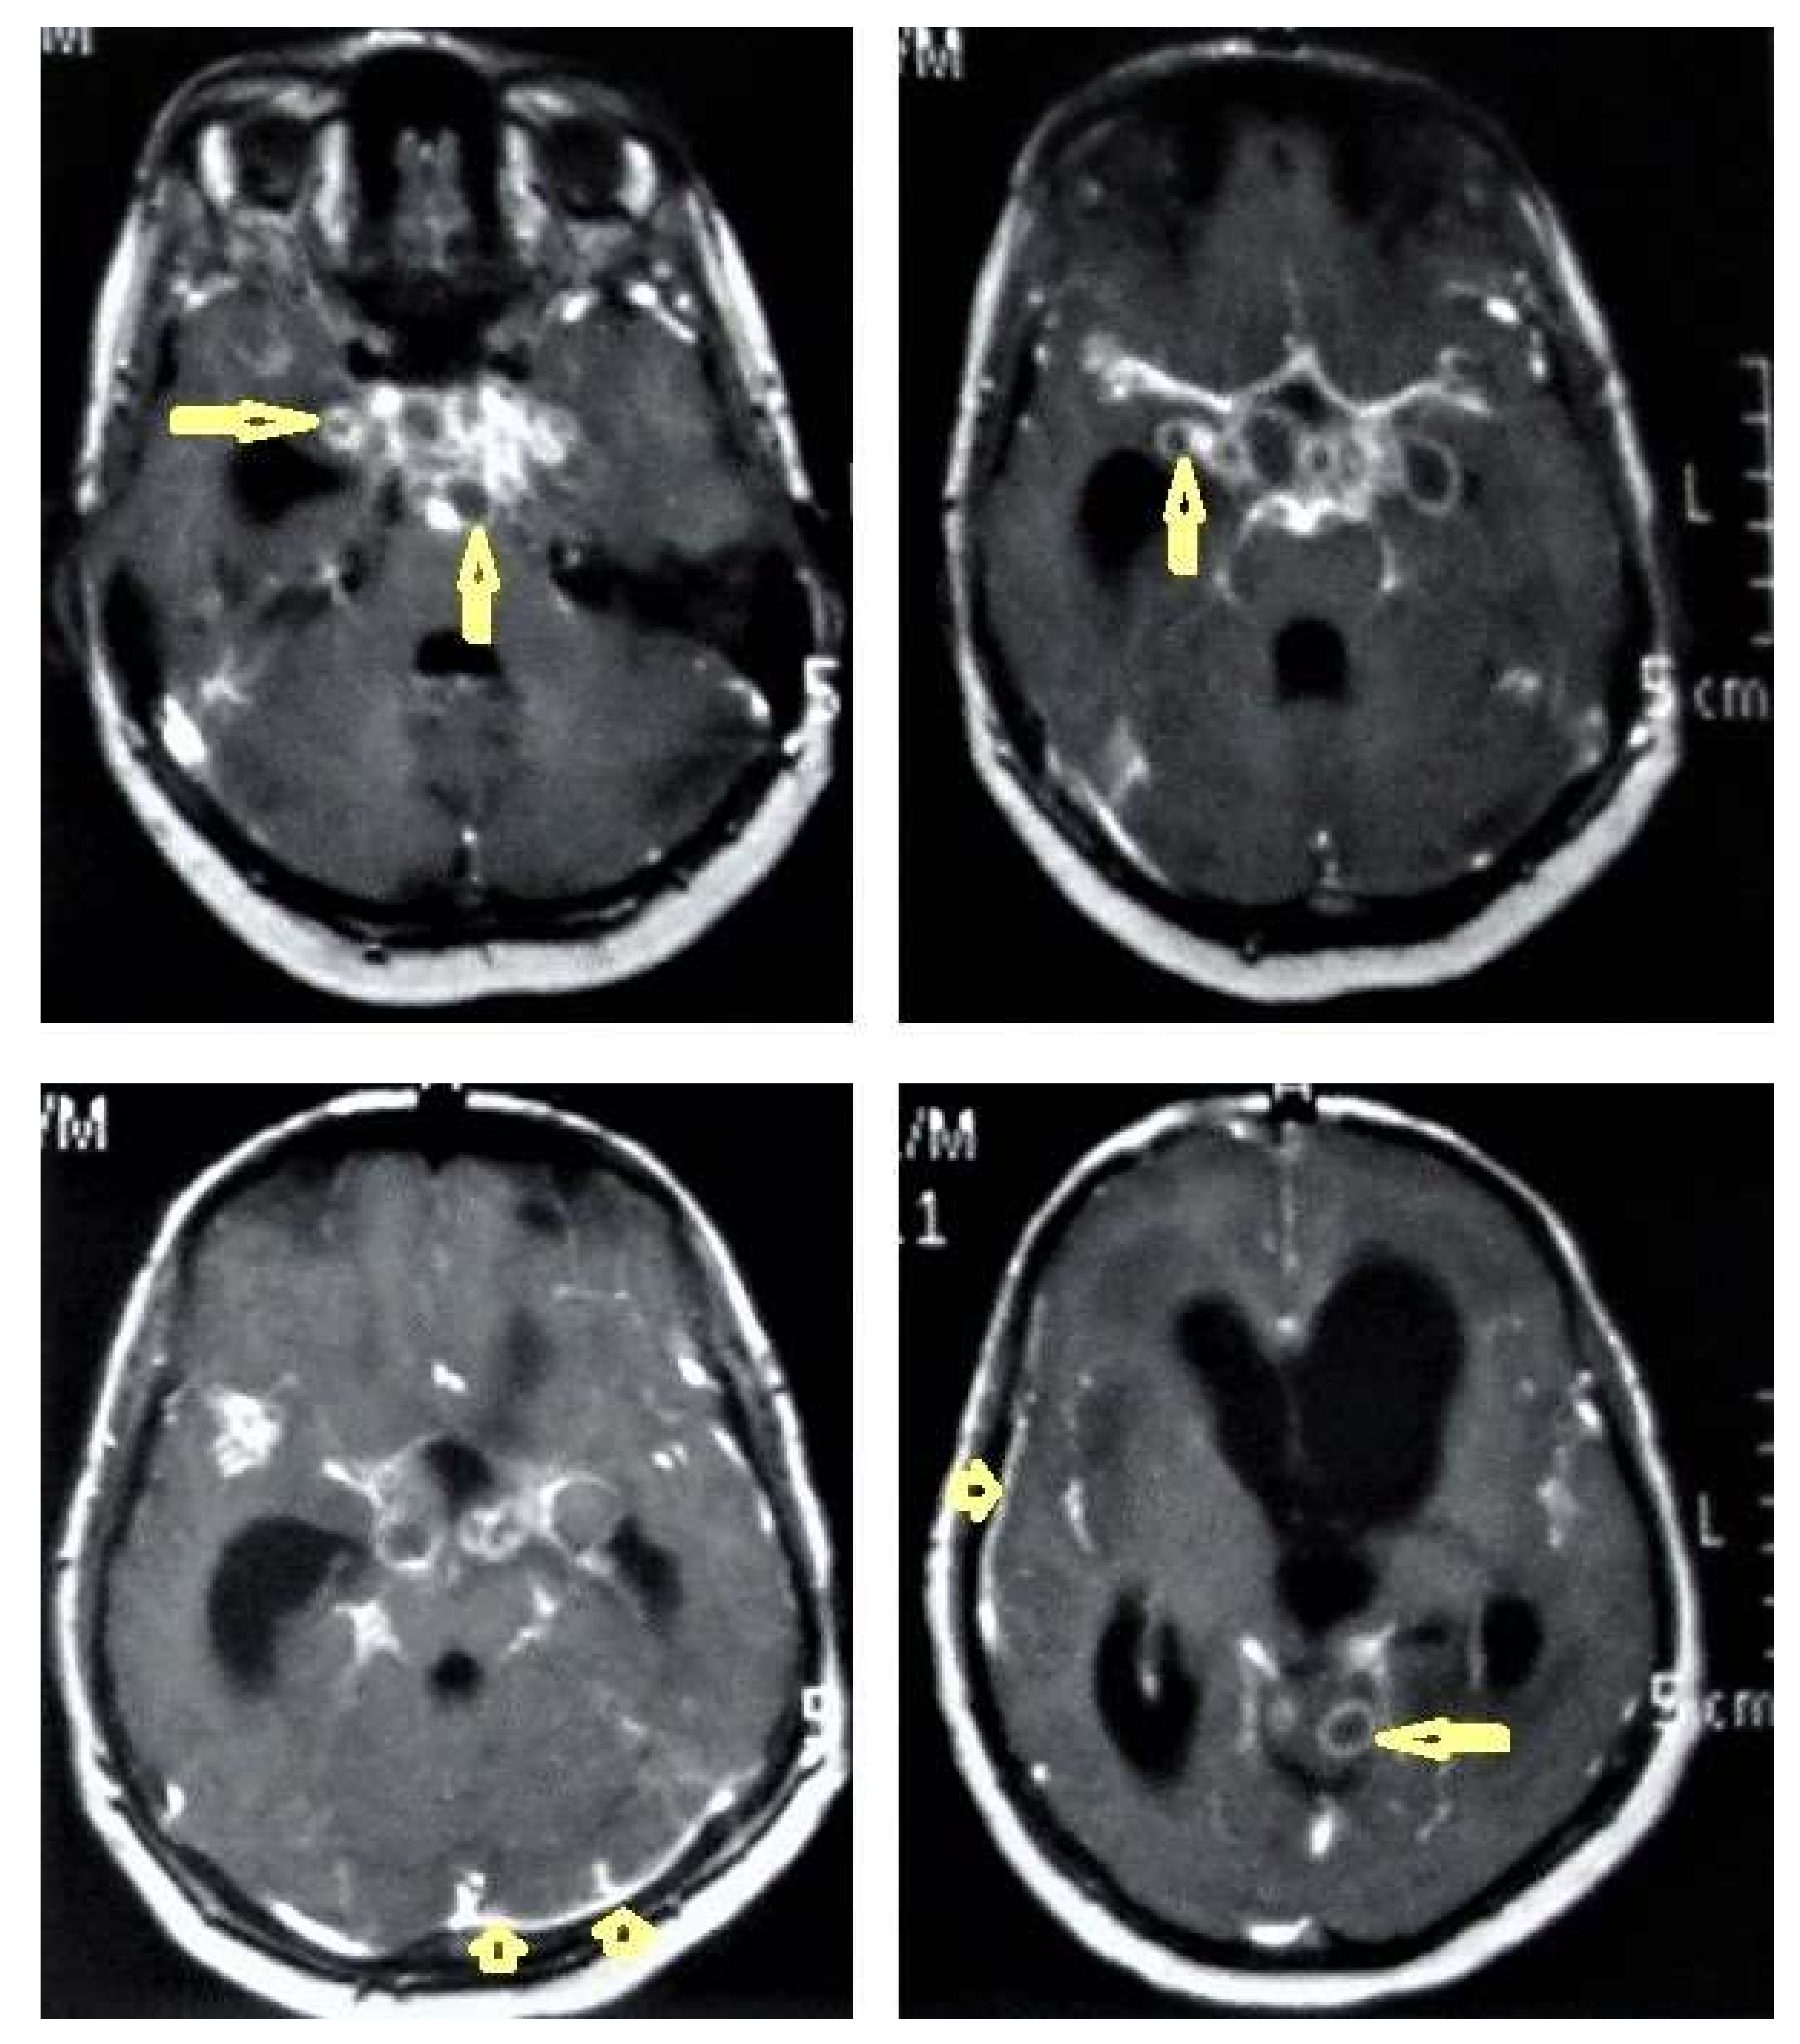

• Tuberculous leptomeningitis (Figure 12) is considered to be one of the most common types of neurotuberculosis. It is frequently seen in children and is associated with complications. On an MRI, it appears as diffusely enhancing exudates and leptomeningeal enhancement with predilection where basal cisterns are involved. Magnetization transfer MRI (MT-MRI) is highly valuable for the diagnosis of mild cases of meningitis [25,27]. Tuberculous leptomeningitis has a wide differential diagnosis, including pyogenic leptomeningitis, fungal leptomeningitis, and leptomeningeal carcinomatosis [28]. It can also mimic sarcoidosis [29].

• Tuberculoma (Tuberculous granuloma; Figure 12 and Figure 13) is one of the most common brain parenchymal tuberculous lesions and can be solitary or multiple anywhere within the brain. It is commonly seen at the corticomedullary junction and periventricular region as a result of hematogenous dissemination. MRI features of tuberculoma vary according the stage of maturation (stage 1, non-caseating; stage-2, caseating granuloma; stage 3, caseating granuloma with central liquefaction; and stage 4, calcified granuloma). Radiologically, each stage of brain tuberculoma can mimic a wide variety of differential diagnoses, such as neurocysticercosis, fungal granulomas, pyogenic abscess, metastasis, glioma, lymphoma, and toxoplasmosis [25,27]. Ring-enhancing lesions of the brain may form a diagnostic dilemma [30].

Figure 12. Tuberculous leptomeningitis. Selected axial T1-weighted images of brain MRI post-contrast administration show diffuse leptomeningeal enhancement (short arrows) with predilection to involve the basal cisterns complicated with hydrocephalus. Multiple ring-enhancing lesions (long arrows) in different regions of the brain.